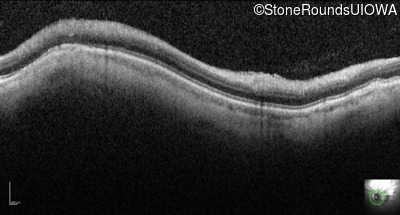

Optical Coherence Tomography - Right - 20/100

Exemplar